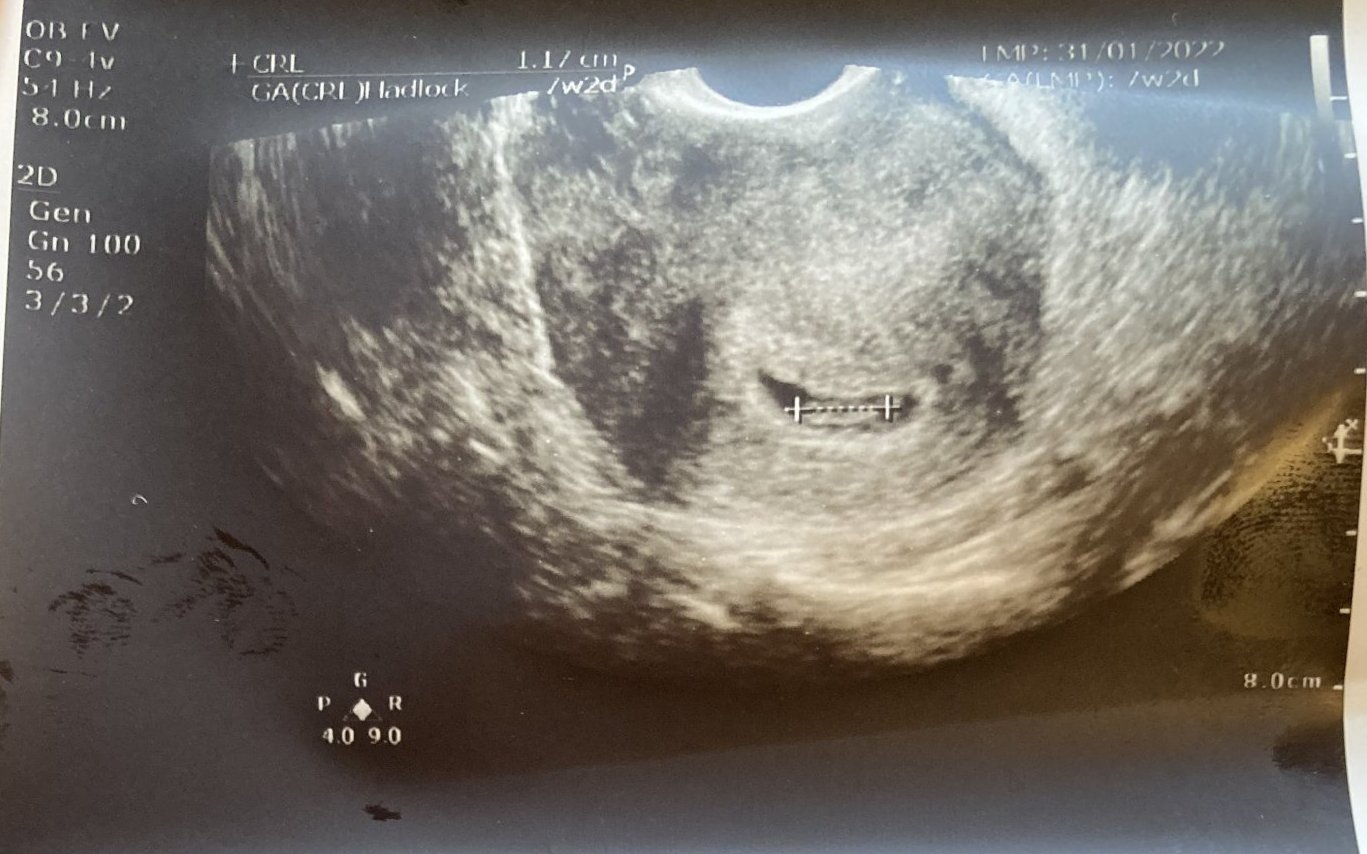

Днес ми беше първият преглед в 8гс и видях ембриончето, чух му пулса. Добре дошли на новите мами и съжалявам за тези, при които приключват бебешките емоции. Не се обвинявайте, бъдете спокойни и следващият път всичко ще е наред! И аз съм била от двете страни и знам какво е. Действително по-силно изразените симптоми означават, че ембрионът се развива. И на мен ми се гади по цял ден, понякога повръщам, лежа почти по цял ден, гърдите ми са подути и болезнени… Лекарката днес ме успокои, че това ще се случва най-късно до 12гс. Предписа ми едни хапчета за гадене “Емил”, но още не съм ги пробвала. Прикачам и снимка, защото някоя от вас искаше снимки с последен цикъл 25.01.22